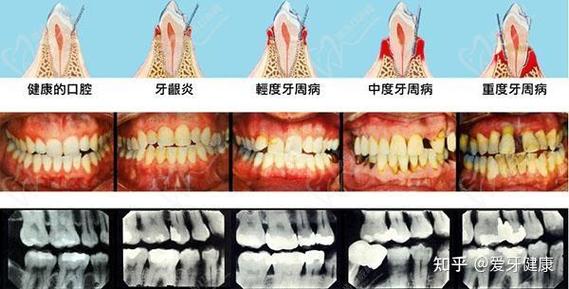

(图片来源网络,侵删)- 这是最直接、最权威的渠道,他们通常掌握最新的本区惠民口腔补贴政策信息,知道申请条件、所需材料、流程以及定点医院名单。

(图片来源网络,侵删)如果您通过街道或区局了解到某家医院是定点机构,可以直接致电该医院的口腔科或客服,询问如何申请补贴项目、需要哪些材料、是否有名额等。